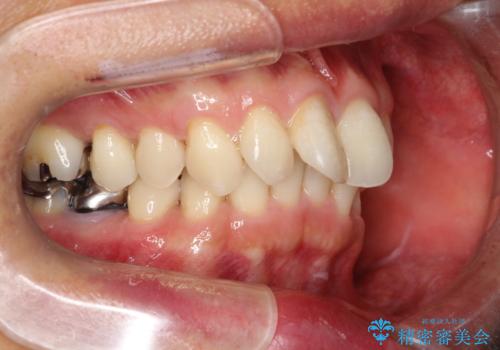

【遠心移動ワイヤー矯正】翼状捻転を治したい

- 前歯の捻れを主訴に来院されました。

顔貌の正中と上顎前歯の正中があっており、下顎は顎位が偏位している状態でした。

小臼歯を抜歯する治療計画も提案しましたが、

今回は患者さんの希望もあり非抜歯にて歯列拡大、遠心移動を行なってできる限り前歯を下げながら配列する治療を行いました。

上顎はリンガルアーチにて遠心移動を行うことで前歯を唇側傾斜させずに配列することができました。